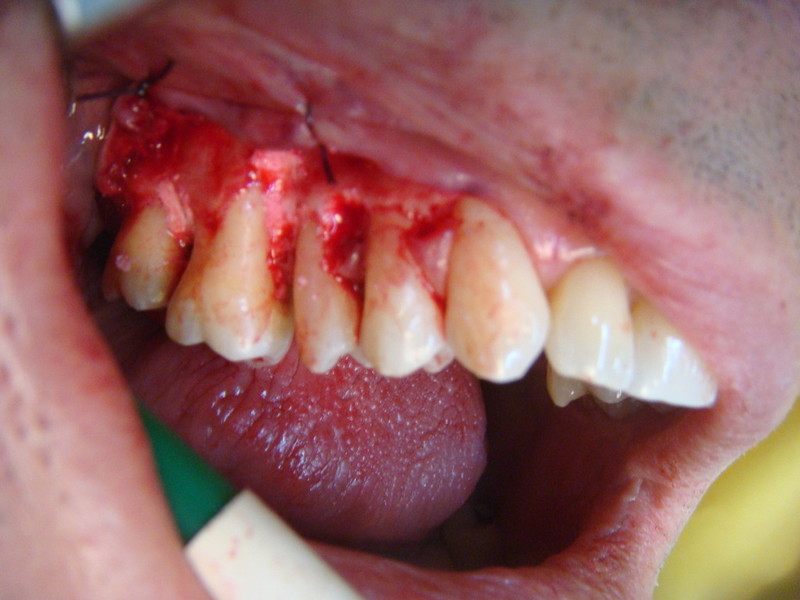

Chirurgia plastica Muco-Gengivale

Rigenerazione Gravi difetti parodontali

Rigenerazione difetto parodontale di un canino inferiore con materiale eterologo